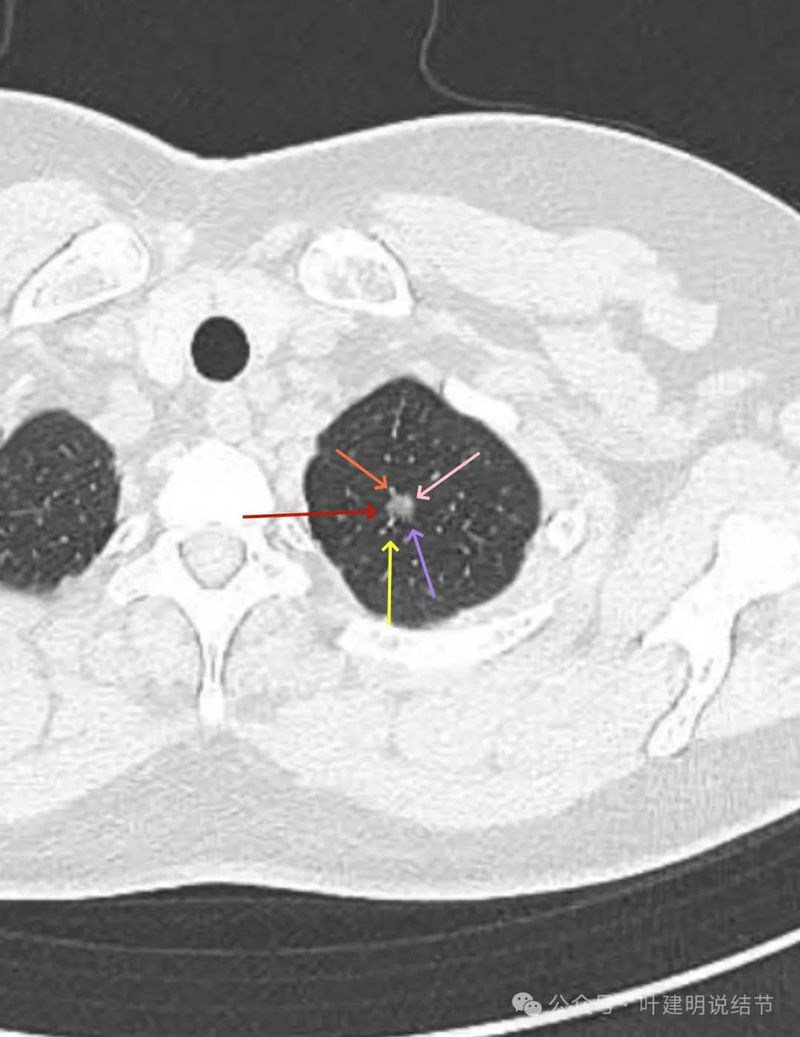

磨玻璃密度,轮廓与边界清,密度稍不均。

边缘部分较淡,有灶内细支气管扩张。

1、诊断问题:此灶发现4个月,随访持续存在,整体轮廓与边界清,是混合密度结节,有血管进入与穿行、有毛刺与小棘突征、灶内与边缘有细支气管扩张、整体密度略显杂乱,而且大部分层面密度较高,偏实性密度。整个病灶看有一定膨胀感。没有卫星灶,没有晕征,也没有片状模糊影。所以基本上考虑是肿瘤范畴,这种密度应该比原位癌要厉害点,至少微浸润性腺癌,也可能是浸润性腺癌含中分化成分以及少许贴壁亚型。